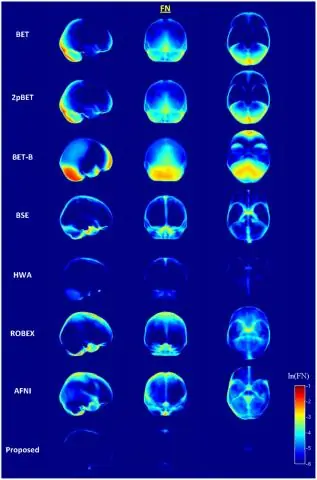

В настоящее время при переходе от использования NFBS в качестве хранилища изображений с раздетыми черепами золотого стандарта к использованию репозиториев IBSR и LPBA40 в качестве источника изображений золотого стандарта на рис. 3 показаны блок-графики коэффициентов подобия костей для BET, 3dSkullStrip, HWA, BEaST с использованием beast-library-1.1 и BEaST с использованием NFBS в качестве библиотеки приоров. Для IBSR 3dSkullStrip работает лучше, чем BET и HWA, аналогично NFBS. Однако для LPBA40 BET работает намного лучше, чем два других алгоритма. Метод BEaST был также применен к анатомическим данным в этих репозиториях с использованием двух различных методов: сначала с исходной библиотекой beast-library-1.1, установленной в качестве предыдущей библиотеки, а затем со всей NFBS, установленной в качестве предыдущей библиотеки.

Рисунок 3

Коэффициенты кости для IBSR и LPBA40. Блок-диаграмма коэффициентов Dice для BET, 3dSkullStrip, HWA, BEaST с использованием beast-library-1.1 и BEaST с использованием NFBS в качестве библиотеки приоров. Один субъект был исключен из расчета Dice для каждого из следующих: BEaST с beast-library-1.1 на IBSR (IBSR_11), BEaST с beast-library-1.1 на LPBA40 (S35) и BEaST с NFBS на LPBA40 (S35)

Для метода BEaST использование NFBS в качестве предыдущей библиотеки привело к более высоким средним коэффициентам подобия костей и меньшим стандартным отклонениям 2. Различия в коэффициентах кубиков между наборами данных могут быть связаны с размером и качеством исследования NFB, а также с патологией и возрастом участников. В частности, библиотека приорусов NFBS отражает гораздо более широкий круг индивидов, чем beast-library-1.1, которая содержит только 10 молодых особей. Также могут быть различия в стандарте масок, такие как длина ствола мозга и включение наружных нервов и пазух.